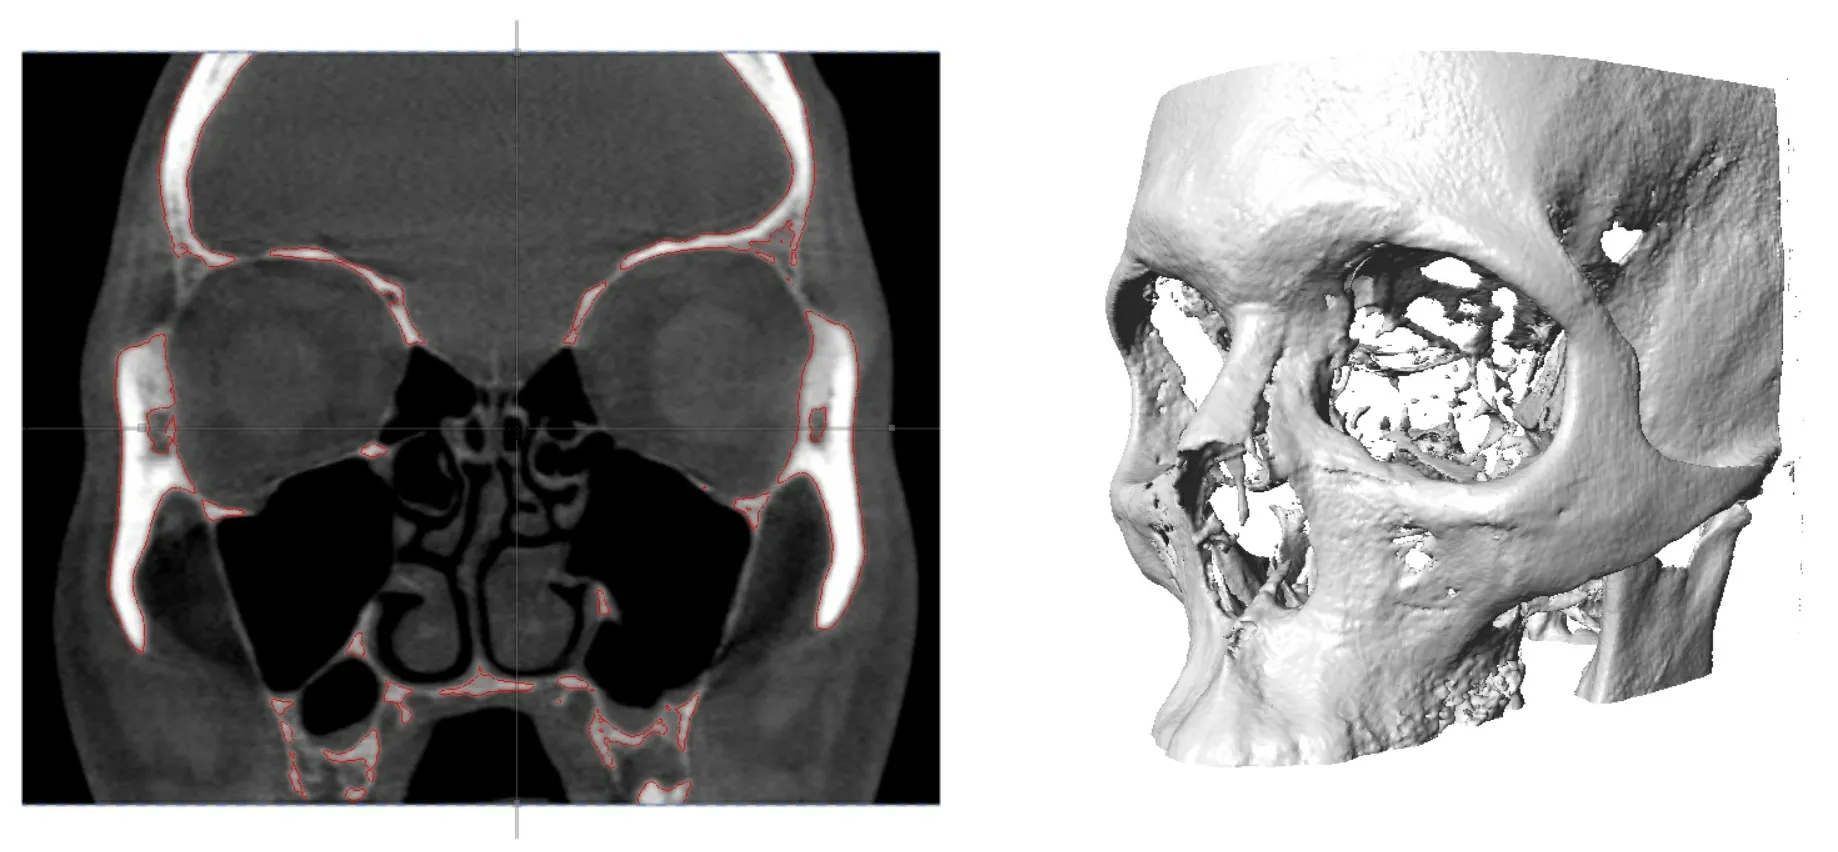

Maxillo

Maxillo is an orbital volume computation application for use by otolaryngologists, ENTs, plastic surgeons, craniofacial surgeons, and maxillofacial researchers. It enables the use of computed tomography (CT) scans of the orbital area to be analyzed as part of diagnostics, pre-surgical planning and post-surgical analysis method.